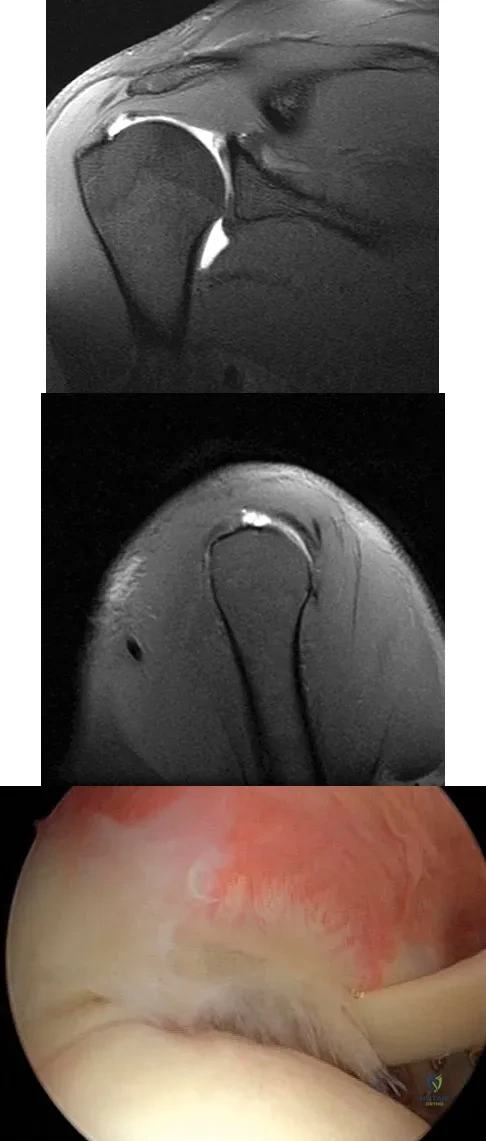

Question 81

Figures 39a and 39b show the MRI scans of a 25-year-old man with right shoulder pain. Figure 39c shows the arthroscopic view from a posterior portal in the beach chair position. What is the most likely diagnosis?

Explanation